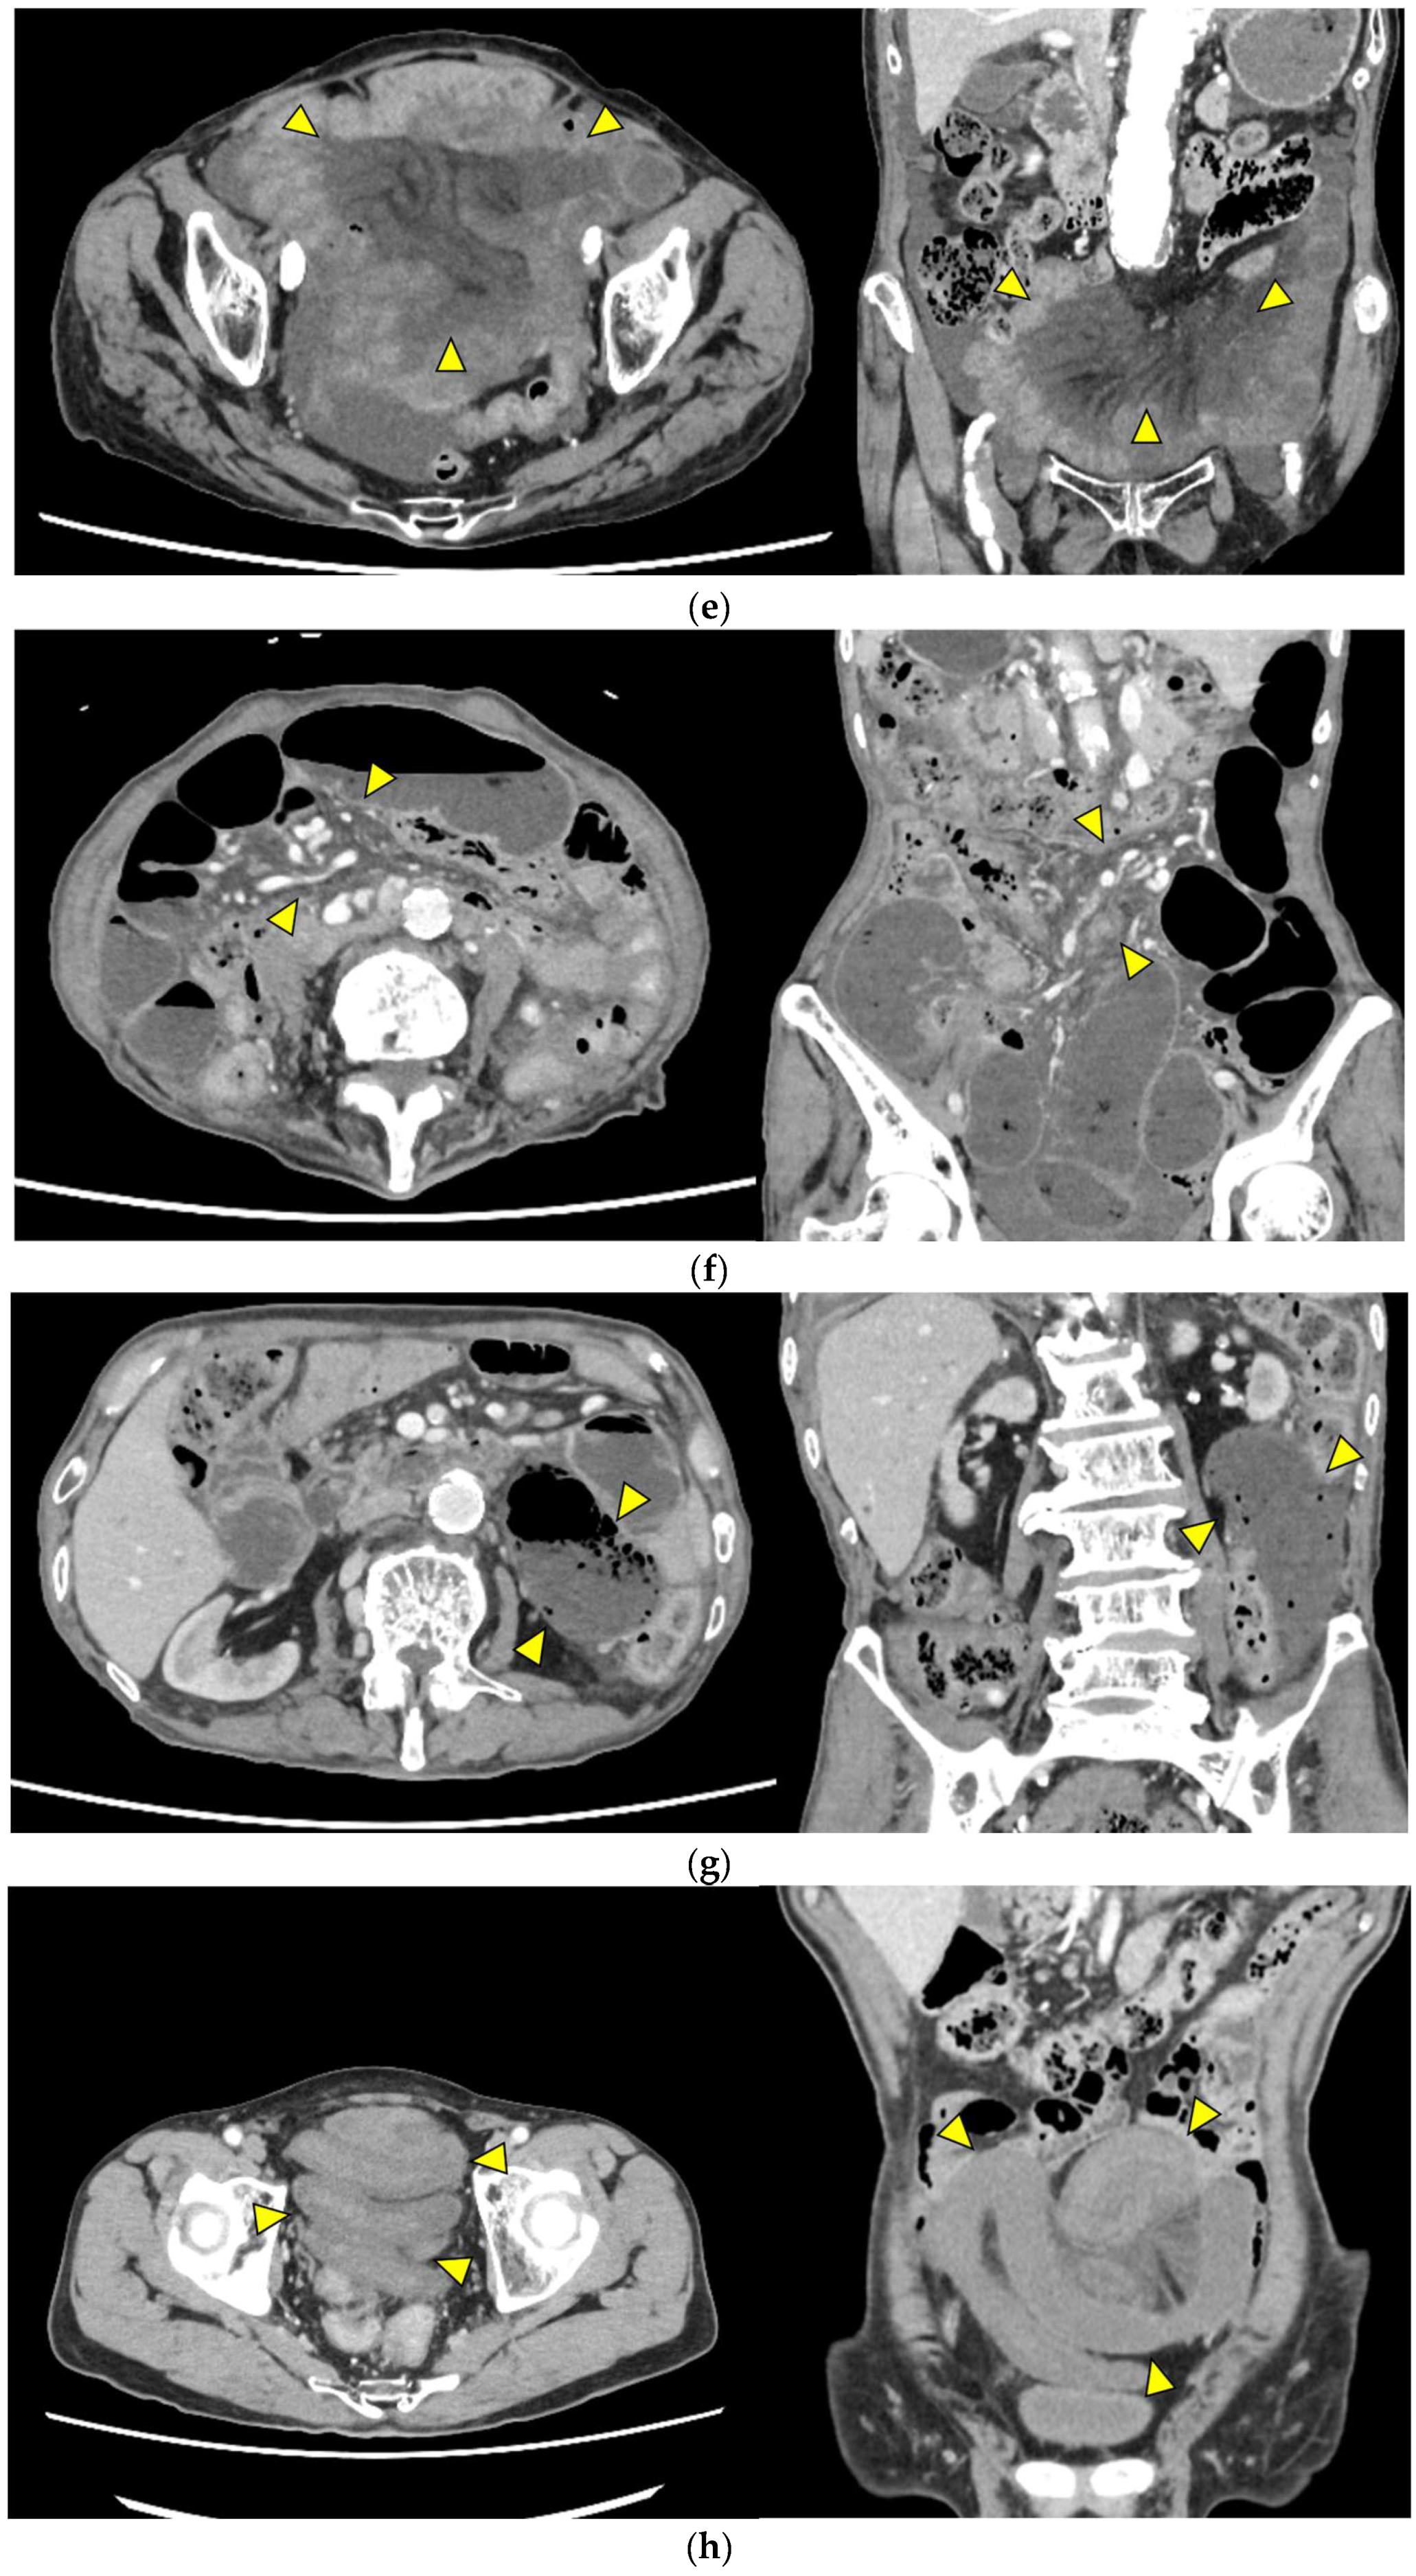

Representative images are presented in Figure 1.

• Closed loop (Figure 1a): A dilated U- or C-shaped bowel segment with two transition points in close proximity, often associated with radial distribution of mesenteric vessels. This configuration may carry a high risk of rapid progression to strangulation and ischemia, requiring prompt surgical consideration.

• Beak sign (Figure 1b): Gradual tapering of the bowel lumen or contrast column at the obstruction point, typically indicating torsion or sharp angulation. This sign localizes the obstruction and often reflects mechanical blockage due to adhesions or volvulus, which may progress to ischemia if left untreated.

• Whirl sign (Figure 1c): Swirling of mesenteric vessels and fat, suggestive of volvulus or twisted mesentery. Presence of this sign strongly suggests torsion with compromised mesenteric blood flow.

• Small bowel feces sign (Figure 1d): Mixture of gas and particulate matter (resembling feces) within a dilated small bowel loop proximal to the obstruction, indicating delayed transit. This sign indicates subacute or prolonged obstruction, but does not necessarily imply ischemia.

• Mesenteric edema (Figure 1e): Increased attenuation and stranding of mesenteric fat surrounding the affected loop, typically reflecting venous congestion. This is an early indicator of impaired venous outflow and increased risk of ischemia, requiring close monitoring and a low threshold for surgical intervention if clinical deterioration occurs.

• Mesenteric vessel engorgement (Figure 1f): Prominent or dilated mesenteric veins near the involved segment, suggestive of impaired venous outflow or strangulation. Venous congestion typically precedes arterial compromise, and the presence of this sign indicates evolving mesenteric ischemia.

• Absent bowel wall enhancement (Figure 1g): Complete absence of bowel wall enhancement on contrast-enhanced CT, which is highly suggestive of transmural infarction. This is a critical sign of irreversible ischemia and generally indicates the need for immediate surgical intervention.

• Blurred Kerckring folds (Figure 1h): Indistinct mucosal folds (valvulae conniventes) in dilated small bowel loops, often associated with ischemic edema. Blurring of mucosal folds reflects mucosal/submucosal injury from ischemia and impending bowel damage due to severe obstruction.

Figure 1. Representative CT findings suggestive of SSBO. Yellow arrowheads highlight the relevant findings. (a) Closed loop; (b) beak sign; (c) whirl sign; (d) small bowel feces sign; (e) mesenteric edema; (f) mesenteric vessel engorgement; (g) absent bowel wall enhancement; (h) blurred Kerckring folds; (i) ascites.